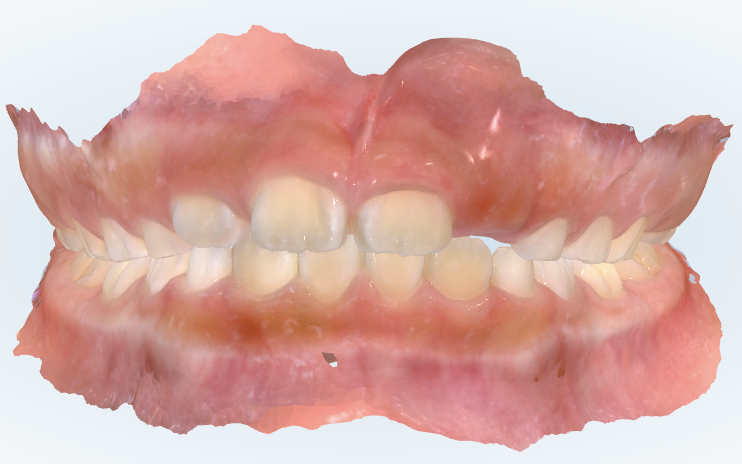

初診時の画像診断

歯のガタガタはあまりありませんでした。

噛み合わせが深いため、下の前歯の先端が上の前歯の内側の歯茎に当たっていました。

上下の前歯の真ん中のラインがずれていました。

スキャンして見てみると、ガタガタは強くありません。現状、歯の並びは良い方です。

ただ、気になるのは前歯の噛み合わせの深さですね。

しかし今は、前歯同士が当たっていません。下の前歯の先端が上の内側の歯ぐきに当たりそうな深さになっています。